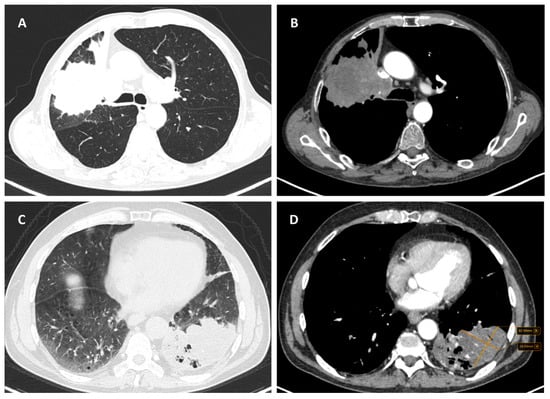

Considering the exclusion criteria previously mentioned, a total of 58 patients were analysed in this study, in which 26 cases were pathologically proven to be adenocarcinoma (Figure 1), 22 cases were shown to be squamous cell carcinoma (Figure 2), and 10 cases were shown to be small cell lung cancer (Figure 3).

Figure 2.

Axial CT of two different cases of squamous cell carcinoma: (A,B) show a right hilar mass with cavity and air bubbles inside, with invasion of the hilar vessels and right main bronchus extending over less than 2 cm from the carina; and (C,D) show a left hilar mass with atelectasis, necrosis, septal thickening, and important invasion of the pulmonary trunk and left pulmonary artery.